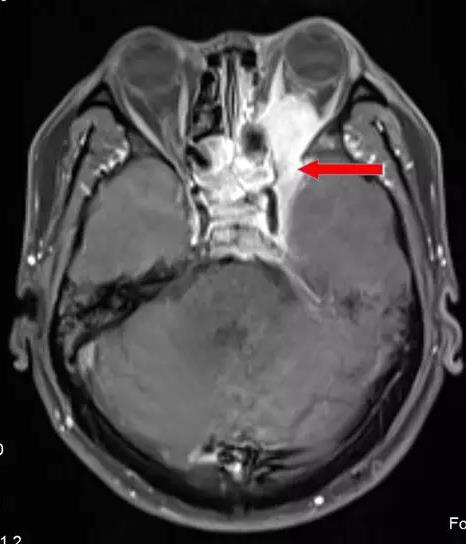

海綿竇位置影像顯示 (橫斷面),增強磁共振圖像(下圖中紅圈內高信號區即右側海綿竇)

腫瘤累及右側海綿竇及臨近腦膜。